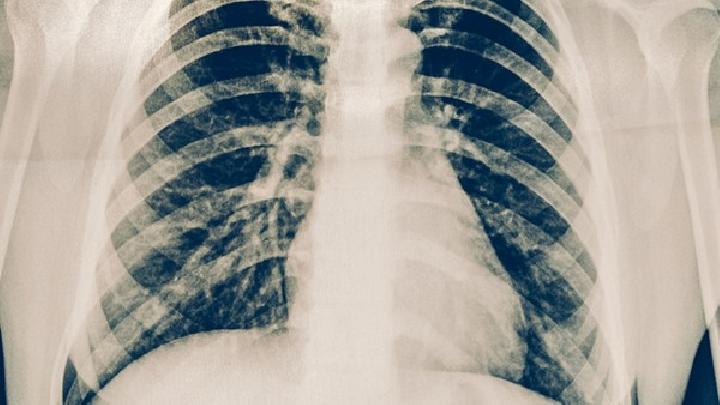

肺栓塞常用的检查方法有什么呢,我们应该去了解,我们都知道针对于肺栓塞这种疾病来说是一种循环系统疾病,同时也是一种呼吸系统疾病,如果您想护理好肺栓塞这种疾病,我们就需要了解这是一种什么疾病,而且知道怎么去检查肺栓塞,那么肺栓塞怎么检查呢,我们一起来了解一下。

当无法诊断是否有慢性肺栓塞时,可以通过很多的方法判断慢性肺栓塞疾病,如果出现慢性肺栓塞疾病的情况时,说明疾病已发生,患者在平时要多加注意身体的调养不要让病情恶化,下面就为大家详细介绍怀疑肺栓塞常见的检查是什么?